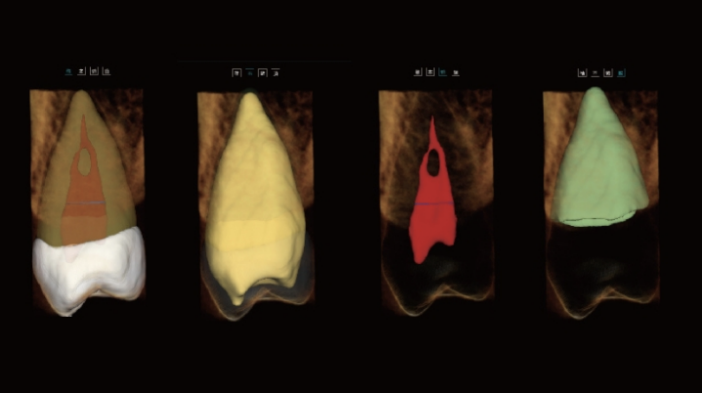

Inclui o Módulo Endo Easy*

Análise Dentária 3D Abrangente: segmentação completa do dente com medições automáticas, planeamento do percurso de acesso e avaliação precisa de cáries.

Visualização Endodôntica Avançada: observação 3D de cáries interproximais, defeitos estruturais e morfologia dos canais radiculares, garantindo que nenhum canal passa despercebido.

Segmentação Completa da Estrutura Dentária: realce automático do esmalte, dentina, polpa e estruturas periodontais, permitindo a visualização das alterações morfológicas.

Mapeamento Avançado dos Canais Radiculares: visualização clara dos canais MB2 e em forma de C, apoiando um tratamento endodôntico preciso e minimizando o risco de canais não detetados.

Visualização Especial dos Canais Radiculares

vermite a visualização de morfologias especiais dos canais radiculares (MB2 e canais em forma de C), orientando os procedimentos endodônticos.

Ajuda a evitar a omissão de canais.

Medição Automática do Canal Radicular

Medição do Canal Radicular: precisa, automática e fiável — evita erros manuais e permite o planeamento pré-operatório.

Planeamento Endodôntico Inteligente: mede com precisão o comprimento do canal radicular, garantindo um tratamento previsível e eficiente.

Simulação de Acesso ao Canal Radicular

Apresenta dinamicamente as posições dos orifícios dos canais radiculares, auxiliando a educação do paciente.

Apoia os clínicos no planeamento do tratamento e na definição da estratégia terapêutica.